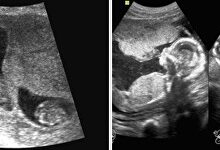

![]() Ecografía de mellizos. | Youtube

Ecografía de mellizos. | Youtube

Los familiares presionaron para que se hicieran pruebas de ADN ante las diferencias tan grandes entre los dos bebes.